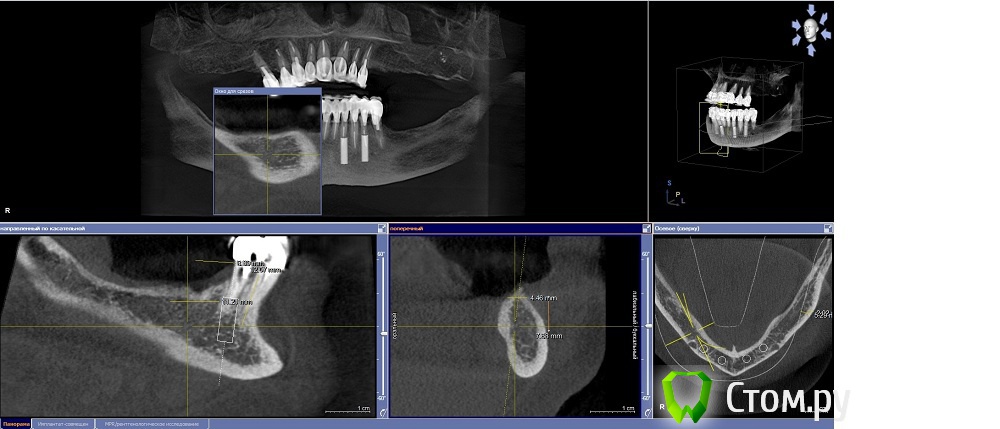

Dr.Sham Опубликовано 14 октября, 2014 Поделиться Опубликовано 14 октября, 2014 (изменено) Планируется удаление всех зубов на НЧ. Пациентка хочет несъемную конструкцию.Вот нарезка.Планируется имплантация Ankylos в позициях 46, 44, 42, 32, 34, 36.В боковых отделах дефицит всего.Думаю удалить зубы через один, чтобы на них временная конструкция держалась, а в промежутках имплантаты.В переднем отделе узко, либо узкие ФДМки, либо заглушка и в овоид край времянок или закрыть свободным трансплантатом.Что думаете?В боковых отделах вопрос...короткие имплантаты и НКР? От сложной костной пластики пациентка отказывается категирочески. Сверху пациентка так же хочет несъем. Поэтому все на 4-х, наверное, не самамя удачная конструкция здесь. Зубы сохранить никак, преп под десной местами по 3 мм. ну и дентин весь мягкий. Изменено 14 октября, 2014 пользователем Dr.Sham Ссылка на комментарий